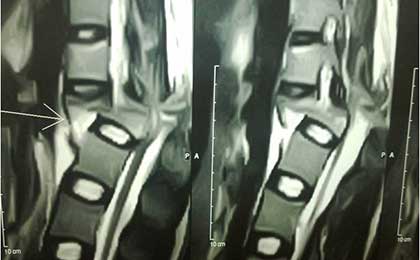

L5 S1 DEG LYSIS LISTHESIS

PRE OP L5-S1 MRI